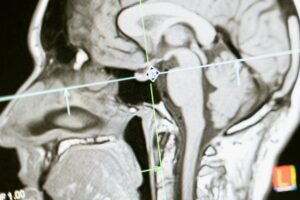

Neuroradiologiska och odontologiska enheten

Close-up of an MRI scan showing a sagittal view of the human brain for analysis.

Enheten för Gastro-, urologi- och thoraxröntgen är en del av verksamhetsområde Bild och Funktion vid Skånes universitetssjukhus i Lund. Här utför vi radiologiska undersökningar med inriktning mot mag- och tarmkanalen, urinvägarna samt hjärta och lungor. Med hög specialistkompetens och modern teknik bidrar vi till säker och effektiv diagnostik som stöd för vidare utredning och behandling.